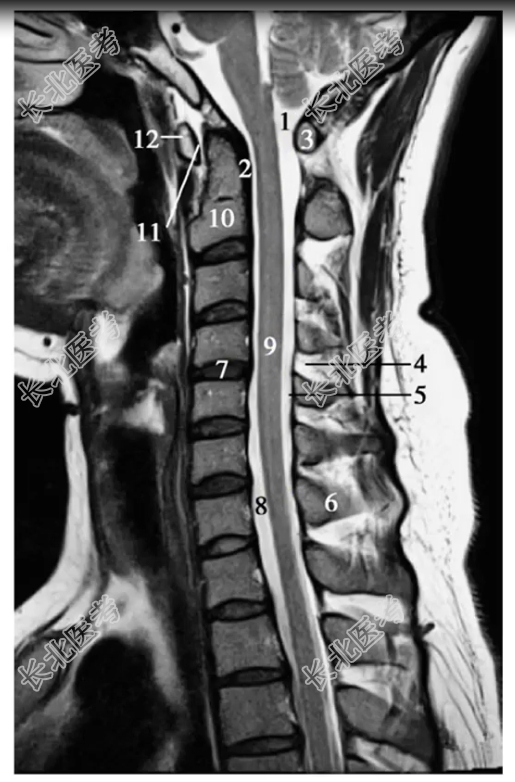

- 单项选择题经脊柱颈段的正中矢状断层MRIT,加权像中,标记为1、8、9的结构分别是

A、小脑延髓池、蛛网膜下隙、脊髓

B、脊髓、小脑延髓池、蛛网膜下隙

C、蛛网膜下隙、脊髓、小脑延髓池

D、小脑延髓池、脊髓、蛛网膜下隙

E、寰椎横韧带、蛛网膜下隙、脊髓